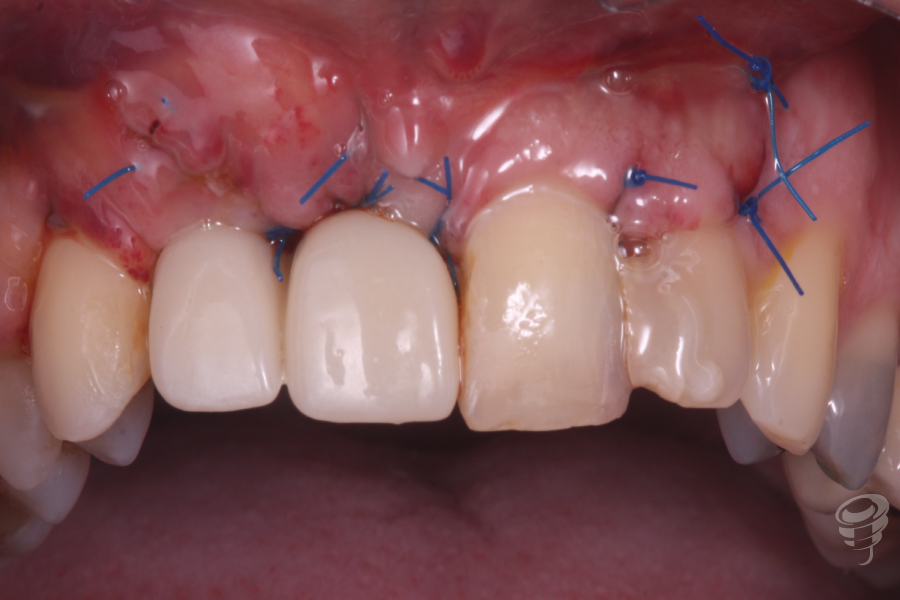

Una vez estabilizado el tornillo Tent Pole, manteniendo la distancia al hueso remanente, procedemos a rellenar con hueso autólogo de fresado y xenoinjerto. Posteriormente colocamos una membrana de colágeno fijada con chinchetas. (Imagen 7 y 8). Finalmente procedemos a realizar la sutura.

Ese mismo día, se le coloca una prótesis provisional fija atornillada (Imagen 9 y 10)

Además en esta cirugía realizamos un injerto de tejido conectivo para ganar más volumen en sentido vestibular.